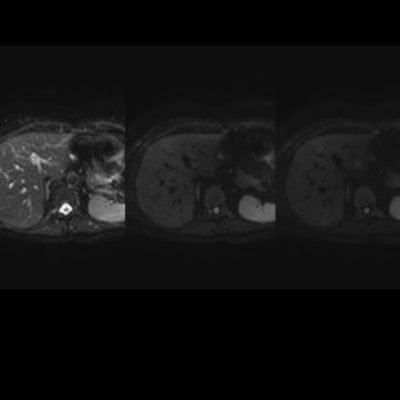

El estudio se complemento con resonancia magnética, donde se demostró la presencia de múltiples imágenes focales hepáticas confluentes con disminución de la señal en secuencias fuera de fase, no mostrando alteración de la señal en secuencias potenciadas en T2, sin signos de restricción al pulso difusión ni refuerzos anómalos luego de la administración de contraste endovenoso, estos hallazgos confirman la sospecha de esteatosis focal multinodular (fig. 5, 6 y 7).